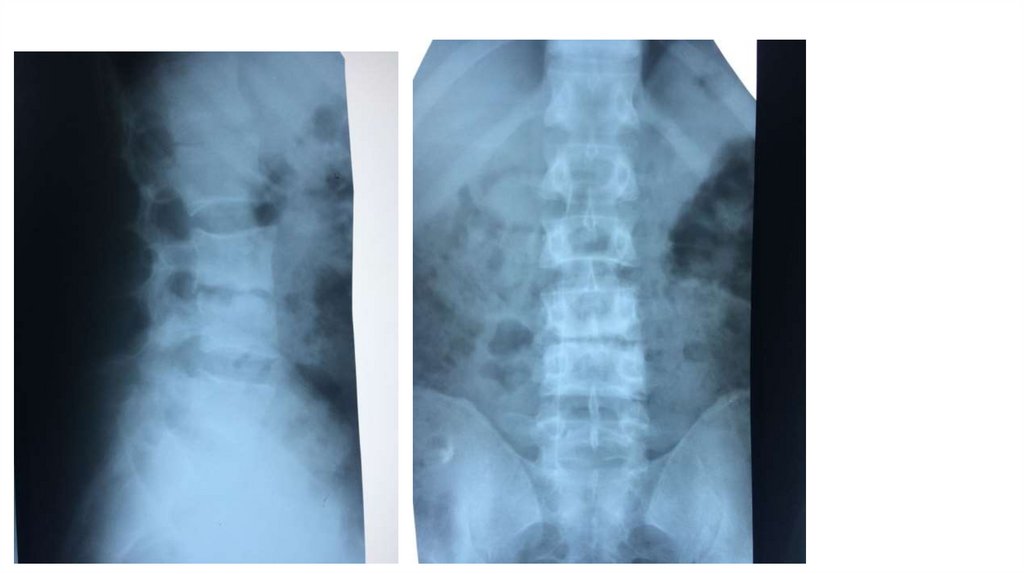

Воспалительные заболевания опорнодвигательного аппарата

заболевания опорнодвигательного аппарата»